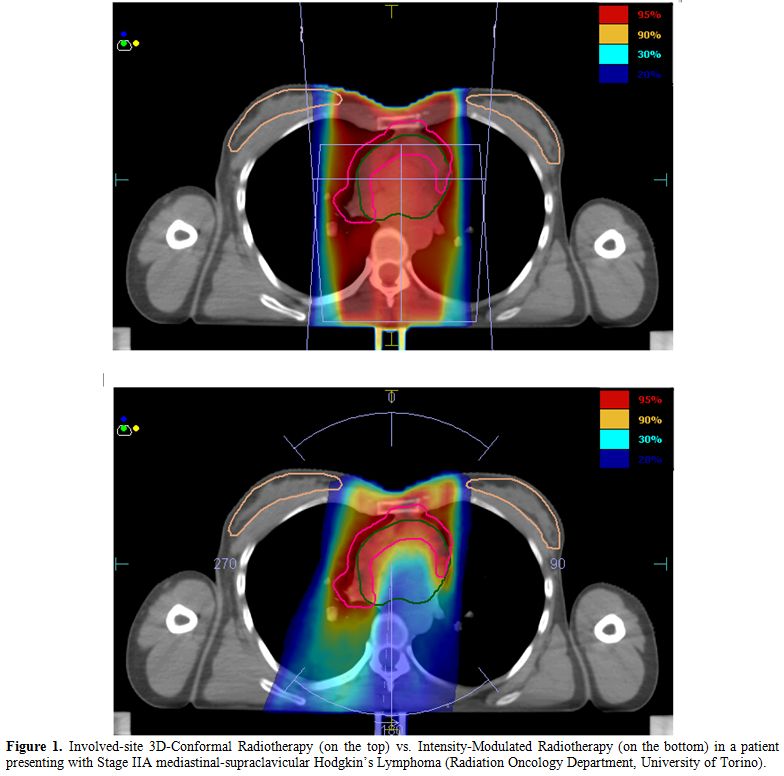

Delivery Of Radiation Therapy Of Large Target Volumes In ...

References 1. Cella L, Liuzzi R, Magliulo M, Conson M, Camera L, Pacelli R, et al. Radiotherapy of large target volumes in Hodgkin's lymphoma: normal tissue sparing capability of ... Get Doc